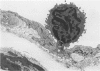

In rats with diet-induced hypercholesterolemia, two concomitant changes began to occur within 1 week and persisted for 1 year: an increase in total plasma cholesterol and an increase in the number of mononuclear cells adhering to the aortic intima (up to values 50 times normal). Adherent cells were approximately 90% monocytes and approximately 10% lymphocytes. Adhesion was focal, with some preference for ostia of aortic branches; it was followed by migration into the subendothelial space. The subendothelial monocytes/macrophages progressively became foam cells, thus giving rise to microscopic "fatty streaks." Ultimately, typical atherosclerotic plaques were formed. Four possible mechanisms of increased cell adhesion are suggested. Endothelial changes were mild; myelin figures arising from the endothelial surface were seen by electron microscopy. Endothelial denudation was never observed, neither in light-microscopic preparations stained with AgNO3 nor by ultrastructure. Platelet participation was minimal. It is concluded that in this model atherosclerotic plaques are initiated by mononuclear cell adhesion and emigration; endothelial denudation is not a necessary step in their pathogenesis.